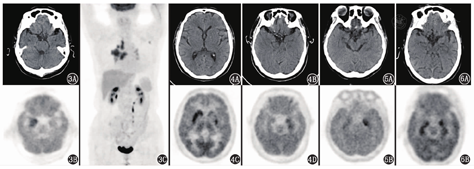

4.自身免疫性脑炎(autoimmune encephalitis, AE)。本例患者有神经系统症状及视力下降,亚急性起病,进行性加重,MRI及PET/CT发现边缘叶等颅内多发病变,因此还需考虑AE(图3)的鉴别。AE可分为3种主要类型:N-甲基-D-天冬氨酸受体(N-methyl-D-aspartate receptor, NMDAR)抗体脑炎、边缘性脑炎(limbic encephalitis, LE)及其他AE综合征[6]。抗NMDAR脑炎为最常见,约占AE的80%,儿童、青年多见,女性多于男性,急性起病,临床表现多样,主要有精神行为异常、言语及运动障碍、癫发作等,部分患者合并畸胎瘤,脑脊液抗NMDAR抗体阳性。LE以精神行为异常、癫发作和记忆力障碍为主要症状,影像学上常可见边缘系统受累,包括抗副亮氨酸胶质瘤失活蛋白1(leucine-rich glioma inactivated 1, LGI1)抗体、抗γ-氨基丁酸B型受体(γ-aminobutyric acid-B receptor, GABABR)抗体、抗谷氨酸脱羧酶(glutamic acid decarboxylase, GAD)抗体相关脑炎等。在LE中,抗LGI1抗体脑炎面-臂肌张力障碍发作(faciobrachial dystonic seizure, FBDS)是该病特征性的癫发作症状,血清和(或)脑脊液抗LGI1抗体阳性;抗GABABR抗体脑炎的临床症状更明显,严重且难治性癫发作是该病的主要特点,约1/3的患者合并小细胞肺癌,血清和脑脊液抗GABABR抗体阳性;抗GAD抗体脑炎临床上主要表现为僵人综合征和小脑共济失调,血清和(或)脑脊液抗GAD抗体阳性。

18F-FDG PET检测AE的灵敏度为87%(80%~92%)[7]。抗NMDAR脑炎可表现为基底节高代谢和弥漫性皮质低代谢的混合模式,双侧枕叶代谢明显减低具特征性,有时脑代谢也可接近正常[8];抗LGI1抗体脑炎大多数高代谢灶位于基底节和内侧颞叶(图4);抗GABABR抗体脑炎主要表现为内侧颞叶代谢增高(图5);抗GAD抗体脑炎多数表现为低代谢,病变主要位于内侧颞叶,少部分患者表现为基底节、颞叶代谢增高(图6)。MRI对AE诊断的灵敏度不如18F-FDG PET[7],可无明显异常,或仅有散在的皮质、皮质下点片状异常信号[9]。